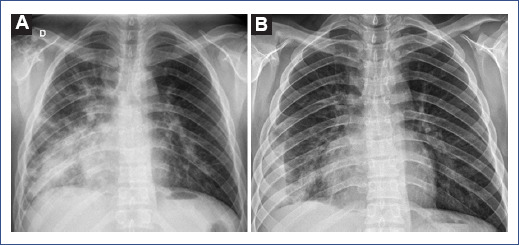

Laboratory results showed elevated acute phase reactants: elevated C-reactive protein, ferritin, and lactate dehydrogenase (LDH). In addition, the coagulation profile showed hyperfibrinogenemia and elevated D-dimer (2.5-fold its normal value). Conversely, prothrombin time and activated partial thromboplastin time within normal ranges, and hemogram and differential count with no alterations (Table 1). Chest X-ray showed multifocal opacities with peribronchial and peripheral distribution with right predominance and right perihilar and paracardiac consolidation associated with small inferior consolidations (Figure 1). Due to the clinical picture and hypoxemia associated with laboratory and radiological findings, the patient was diagnosed with severe COVID-19 pneumonia plus bacterial coinfection. Treatment was initiated with intravenous ceftriaxone 80 mg/kg/day and dexamethasone 0.15 mg/kg/day.

Figure 1 The chest radiograph shows multifocal opacities with peribronchial and peripheral distribution and right predominance. A: right perihilar and pericardiac consolidation associated with small inferior consolidations in the lateral pleural base. B: after treatment, decrease in opacities and right pleural effusion.